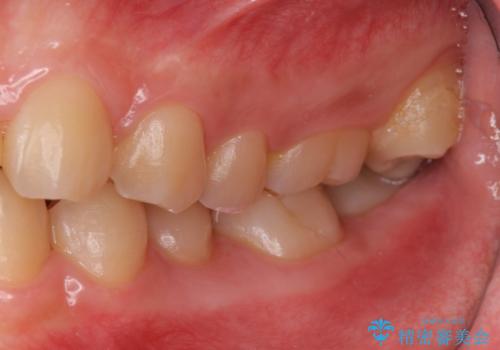

- 歯のがたつきを主訴に来院。

左右とも奥歯のがたつきがあり、左奥はすれ違っていました。

また、右奥は反対咬合になっていました。